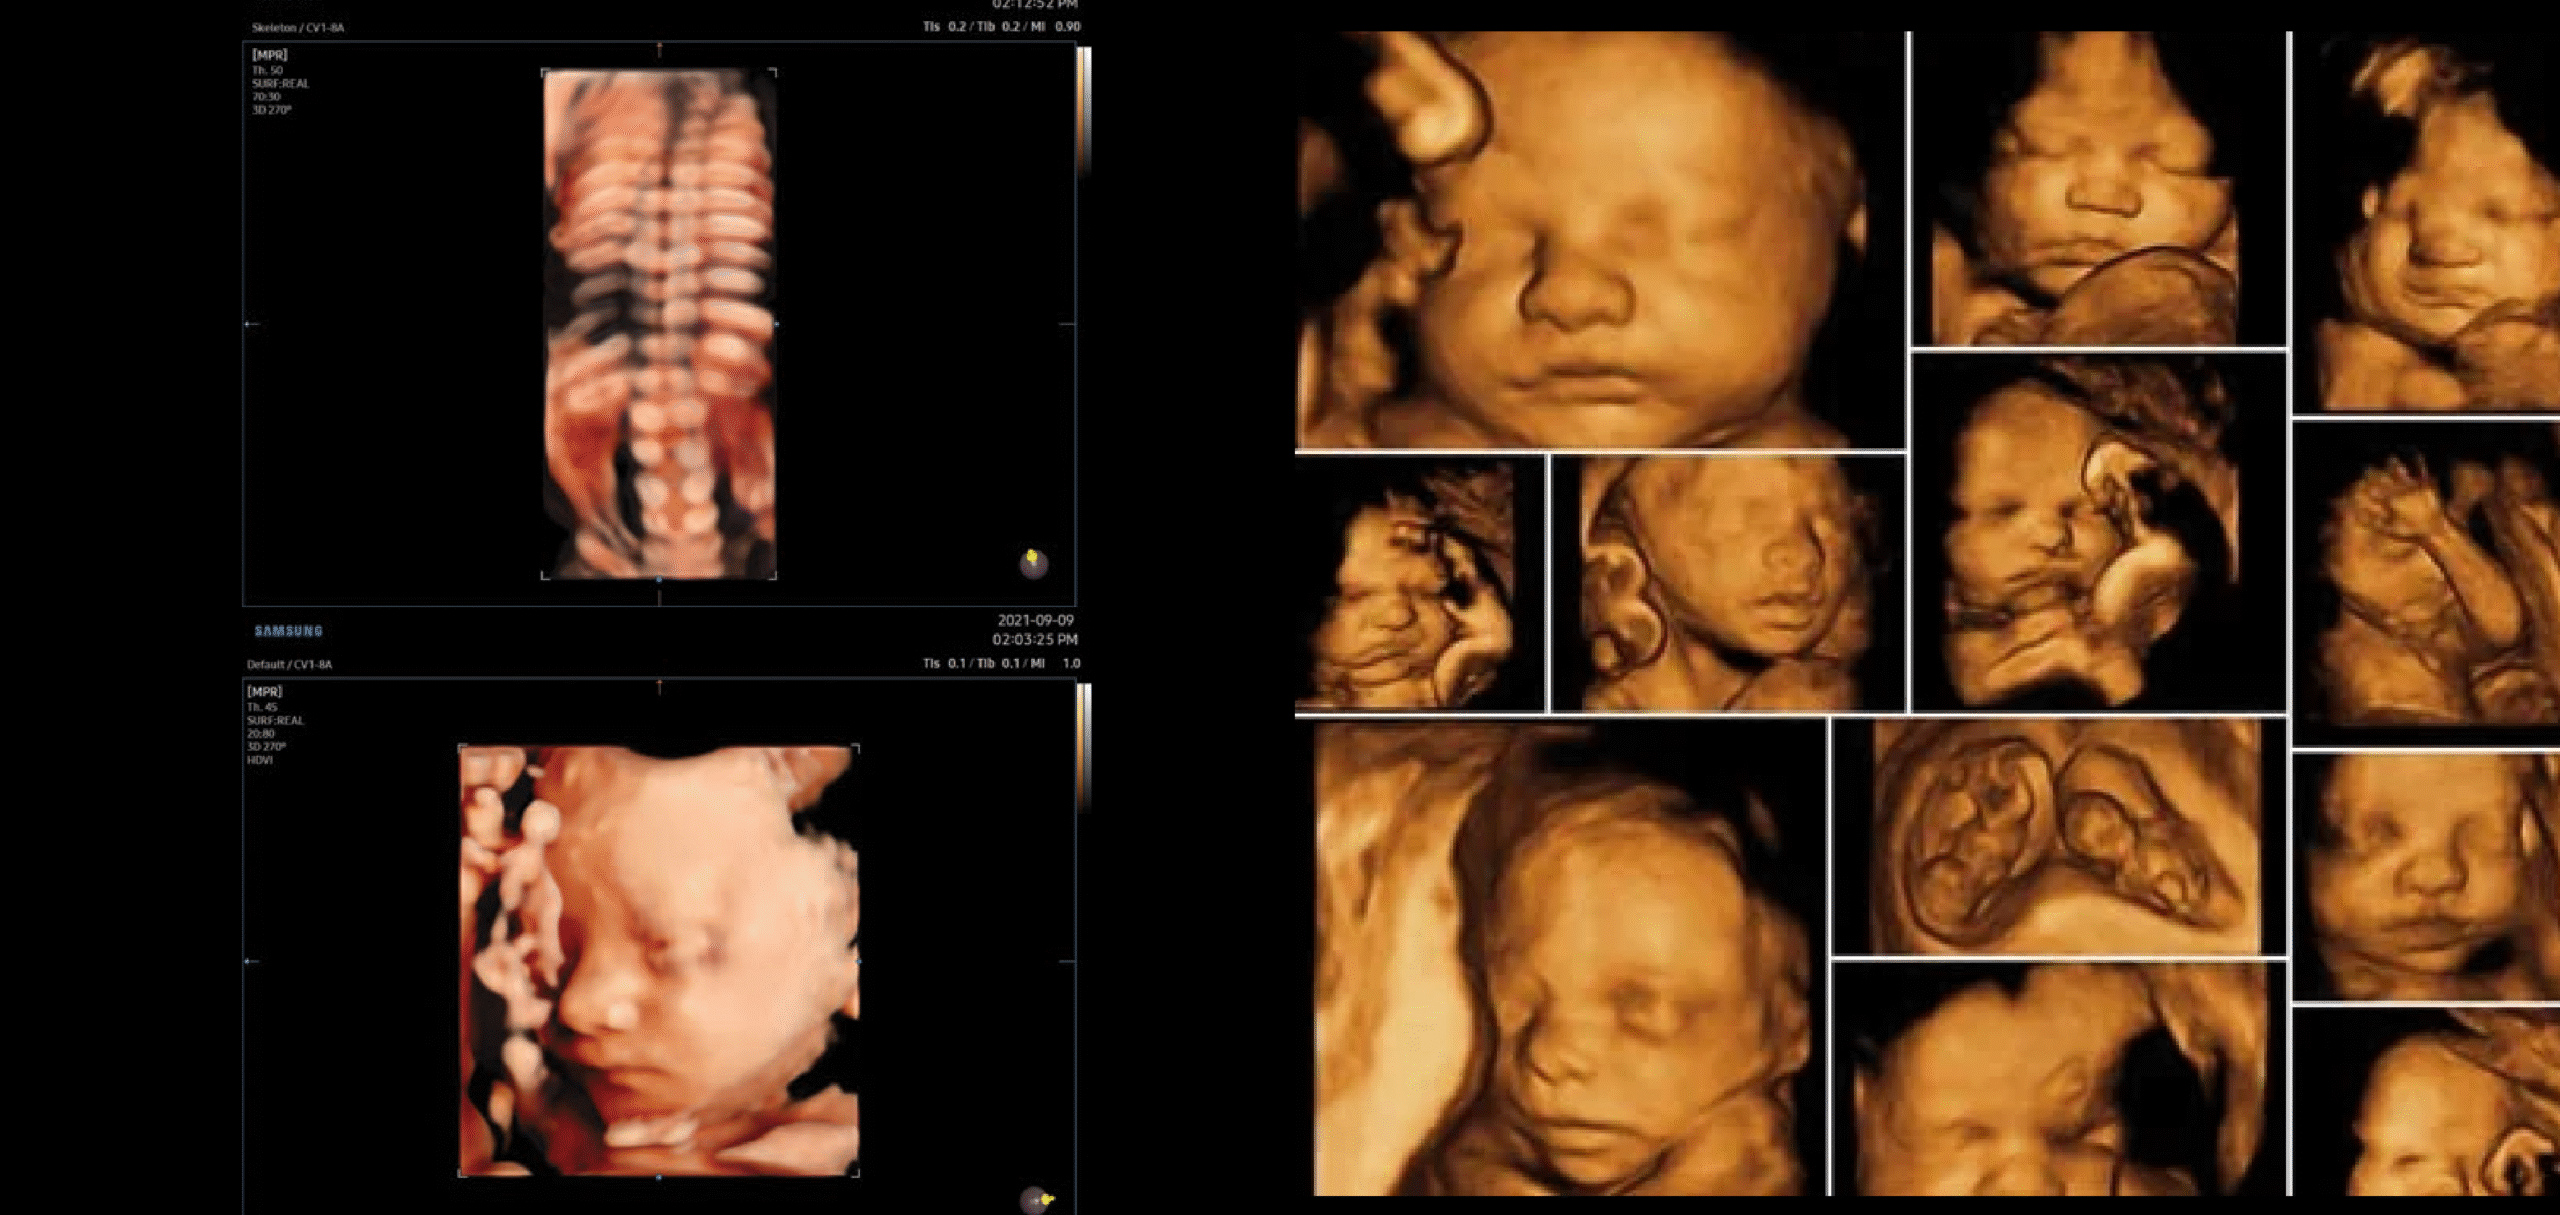

Structural anomalies (craniofacial malformations, limb defects, neural tube defects)

Congenital heart disease and other internal organ abnormalities

Fetal growth patterns and development milestones

Placental and amniotic fluid assessment

Gender determination with high accuracy (as per medical regulations)